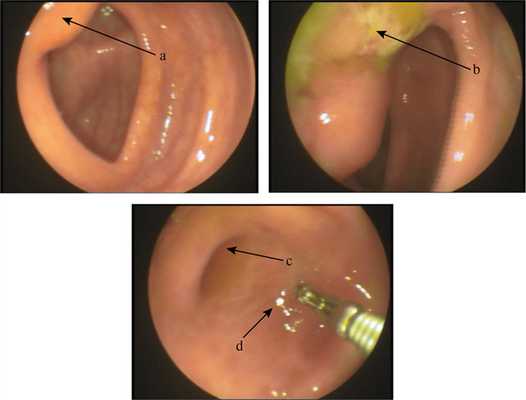

Колоноскопия. При осмотре перианальной области изменений не отмечено. Геморроидальные узлы не увеличены. При пальцевом исследовании прямой кишки болей и патологических образований не выявлено. Тонус сфинктера сохранен. Толстая кишка осмотрена, включая купол слепой кишки. При осмотре со стороны восходящей ободочной кишки особенностей области баугиниевой заслонки не замечено, она имела уплощенную форму (рис. 1). Рис. 1. Больная Ч., 34 года. Колоноскопия. Эндофото. Изменения илеоцекальной области. а — баугиниева заслонка; b — язва; с — устье аппендикулярного отростка; d — купол слепой кишки. Слепая кишка отклонена медиально и деформирована, из-за чего ее форму определить затруднительно. По этой же причине не удалось провести фронтальный осмотр баугиниевой заслонки, но на участке нижней губы баугиниевой заслонки, обращенном к отверстию, выявлена язва (см. рис. 1) средней глубины, неправильной формы, с невыраженным воспалительным валом, ровным дном и налетом серого фибрина. Размеры язвы не определены из-за деформации этой области. Отмечалась повышенная плотность стенки этой области при инструментальной пальпации, перистальтика отсутствовала. Проведение колоноскопа диаметром 1,2 см через отверстие баугиниевой заслонки оказалось невозможным из-за его сужения. Произведен забор фрагментов слизистой оболочки с краев и дна язвы для гистологического и цитологического исследования. Область купола слепой кишки и устья аппендикулярного отростка — без особенностей (см. рис. 1).